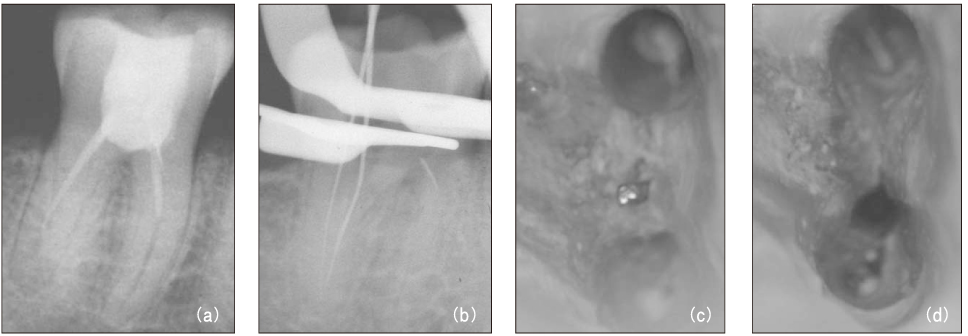

Figure 6

File separation in the canal (a) and root perforation (b). Canal obturation after bypassing with hand file (c, d).

Figure 6 File separation in the canal (a) and root perforation (b). Canal obturation after bypassing with hand file (c, d).